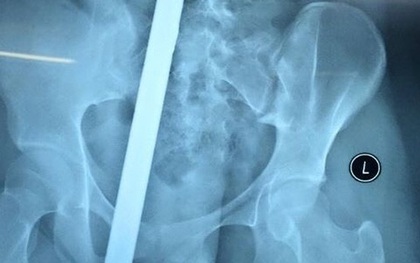

Nữ sinh 16 tuổi bị thanh sắt đâm xuyên người

Trên đường đi học về, một nữ sinh 16 tuổi ở Bắc Ninh đã bất ngờ bị thanh sắt dài từ xe 3 bánh chở vật liệu xây dựng đâm phải. Cú đâm mạnh đã khiến thanh sắt dài cắm xuyên từ mông đến thắt lưng thiếu nữ.